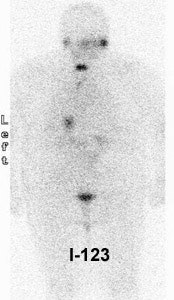

I-123 Diagnostic scan: The diagnostic scan on the left was performed using I-123. Extensive pathologic nodal uptake is seen within the lower neck and mediastinum. A separate focus of increased tracer accumulation is seen over the right upper abdomen (not seen on post-therapy scans- possibly due to superimposed liver activity). The post-I-131 therapy scan (right) demonstrates uptake in the nodal metastases and diffuse hepatic tracer activity due to metabolism of radiothyroxine. |